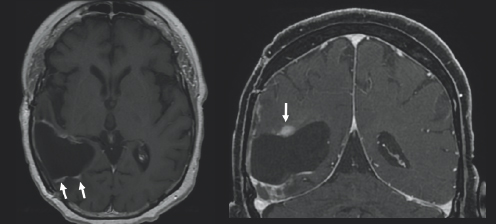

(Left) There is charcoal grey color surrounded by black space and a thin light gray outline. There is a black colored blob in the bottom left side of the image with three white blobs around it; two on the bottom and one on the top. Each white blob is highlighted by white arrows. There is a small light gray circle to slightly to the right of the center of the image. It is circled in white. (Right) There is charcoal grey color surrounded by black space and a thin light gray outline. On the left side of the image, there is a black blob with a white colored blob on top of it. There is a white arrow pointing downward towards the white blob.

FIGURE 3.3 Brain MRI after surgery. Follow-up axial (left) and coronal (right) post-contrast images, obtained 34 months follow-up, show progressive increased size of nodular areas of abnormal enhancement that appear bright after being injected with IV contrast, along the superior and anterolateral margins of the resection cavity (white arrows), with a new abnormal ependymal enhancing nodule in the left frontal horn (white circle), concerning for recurrent tumor.

A month after her surgery, Janet began chemotherapy and radiation treatment. She began trialing different chemotherapy drugs recommended by her team of physicians to pinpoint which would be most effective for her tumor. She was unable to be treated with the standard-of-care drug, TMZ, due to a severe anaphylactic allergic reaction. Despite desensitization to try to ween her on TMZ use, she continued treatment with lomustine, a different chemotherapy drug. Janet was placed on multiple clinical trials starting with the Belinostat/MRSI (magnetic resonance spectroscopic imaging) study and later the 5-ALA (5-aminolevulinic acid) study. Early on in her treatment, Janet turned to tumor treating fields (TTFs), to see if that form of treatment could provide her the benefit of tumor reduction. TTFs are commonly used in the form of an Optune® device. An Optune® device is a physical, white-colored cap that patients can place over their shaved heads to reduce cancer cell growth through the electric fields that the device omits. In the fall of 2019, Janet moved her care from Emory University Hospital and Wake Forest Hospital to the University of Cincinnati Medical Center to follow her neuro-oncologist, Dr. Soma Sengupta, with whom she had formed a close relationship. Due to the progression of her disease Janet underwent a re-resection surgery in March of 2020 and was placed on the adjuvant letrozole drug study. She then started the chemotherapy drug bevacizumab and required stereotactic radiosurgery (SRS) for a new lesion (Fig. 3.2–3.4). She continued care through her doctors in Cincinnati in conjunction with the care she was receiving at Wake Forest Hospital. She felt prepared but nervous each time she underwent imaging because she knew if her tumor had grown, it would result in a change of course to her treatment.